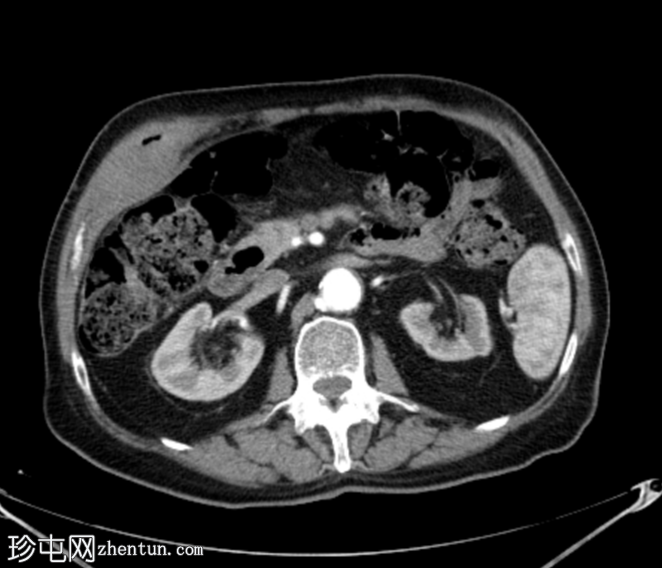

3.png

轴位增强扫描

门静脉期

胆囊底部可见一枚较大的(3厘米)高密度结石,胆囊壁增厚并强化,主要位于胆囊底部。胆囊壁可见一小穿孔,感染扩散至胆囊外,并在肝下区可见气体腔。感染进一步扩散至腹壁肌肉,腹壁肌肉内可见脓肿,边缘强化明显,囊性坏死中心,腔内可见气体腔。十二指肠第一段与炎症胆囊粘连。

检查结果提示急性胆囊炎合并腹壁脓肿。

右侧膀胱有两个小憩室。